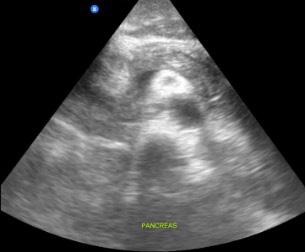

Dr. Artiga’s academic interests include ultrasound, education, and advocacy. Within SAEM RAMS, he has led initiatives such as the Ask-A-Chair educational podcast series, advocacy efforts related to unionization, social media campaigns to promote resident engagement, and the development of board review resources for emergency medicine certification. He has recently taught ultrasound to emergency medicine programs in Latin America.

It was an extremely humbling and eye-opening experience. I went to teach in my father’s country, El Salvador, where I had never visited before. I never truly understood the conditions he lived in beyond his words. All the issues that exist in the U.S. are magnified when you go to countries that don’t have similar resources. Medical decision making is limited by access to resources. It’s not about a lack of capability. I worked with incredibly brilliant doctors who just don’t have access to the same technology or infrastructure we have here. That’s why I believe in supporting ultrasound specifically in these settings. In capable hands, point-ofcare ultrasound can give a clinician life-saving information. Providing this tool and empowering physicians to use it can have a huge impact on individual patients and healthcare systems across the world.

For me, it’s been about chasing my passion and asking, “Who’s on this ride with me?” I’ve always been drawn to ultrasound. Through SAEM’s and the Academy for Emergency Ultrasound’s (AEUS’s) ultrasound didactics and activities, I’ve noticed similar faces showing up. These spaces allow for ideas to connect and develop in ways that don’t happen when you're working alone. You can’t have synergy in isolation. You need people who challenge and inspire you to promote growth. It’s individuals working together, learning from one another, and pushing ideas forward that produce progress.